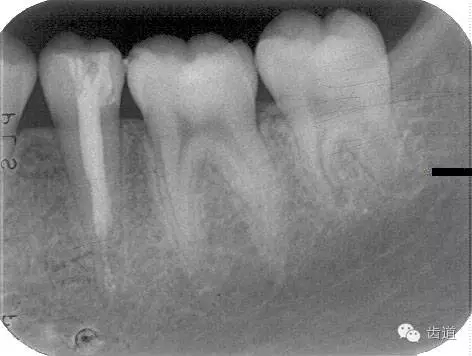

年輕恒牙出現(xiàn)牙髓感染、壞死分解或根尖周病變但牙根尚未發(fā)育完成時(shí),用根管內(nèi)治療的方法誘導(dǎo)牙根繼續(xù)發(fā)育,根尖孔縮小或閉所,稱(chēng)為根尖誘導(dǎo)成形術(shù)。

牙根發(fā)育完成根尖閉鎖后, 應(yīng)及時(shí)改做根管充填術(shù)。由于此種牙齒根管粗大而壁薄,宜選用側(cè)壓充填法lateral condensation method或Ultrafil 3D三維注射式熱牙膠根管充填系統(tǒng)。